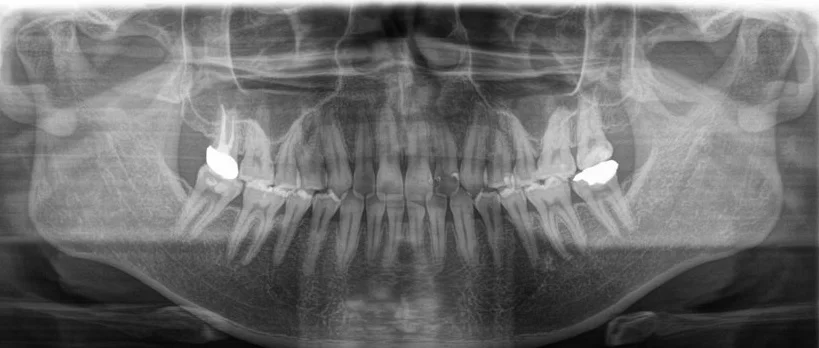

精密レントゲン

虫歯、歯髄、骨が溶けているかどうか、詰め物が適切な状態か、等について1歯ずつ評価を行っていきます。